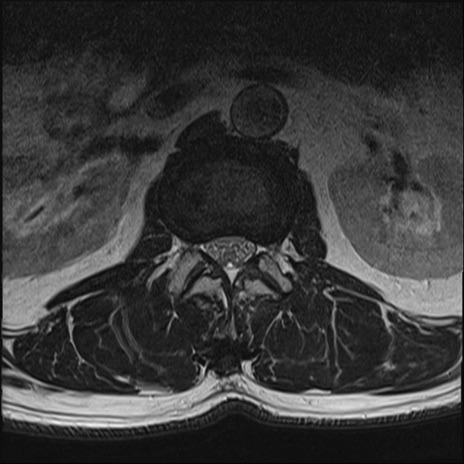

【整形】TIPS症例2 腰椎MRI T2WI(横断像)

【症例】70歳代男性

【主訴】左下肢痛

【現病歴】2週間前くらいから腰痛、左下肢痛あり。左臀部から大腿、下腿外側のしびれが常時ある。歩行とともに同部位の痛みあり。

【身体所見】Lasegue70-/60+、Bragard-/±、PTR ±/±、ATR -/-、IP 5/5、TA 5/4、TS 5/5、EHL 右第1足趾なし/3、FHL 5/5、hypersthesia(-)、足背動脈触知良好

異常所見と診断は?